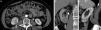

Características particulares de los componentesRadio (R)Este componente representa el diámetro máximo del tumor en cualquier plano. La importancia de la variable en el pronóstico y manejo de los tumores renales es bien conocida, y se utilizó como referencia el sistema de puntuación TNM del año 2002, asignando un punto a las lesiones menores o iguales a 4cm, dos puntos a aquellas entre 4 y 7cm y tres puntos a las mayores o iguales a 7 cm10. Consideramos que la mejor fase para su valoración es la nefrográfica, ya que el realce homogéneo del parénquima mejora la delimitación del tumor (fig. 1).

Componente R: diámetro tumoral máximo (líneas blancas), elegido en cualquiera de los planos. La TCMC del abdomen con contraste endovenoso, en fase nefrográfica, en planos (a) axial, (b) coronal y (c) sagital, presenta una lesión con un diámetro mayor en el plano coronal (40,3mm), por lo que se le asigna un punto. En el plano axial mide 33,4mm y en el sagital 30,5mm.